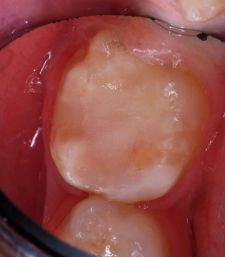

Finished RMGI bioactive ionic resin-based composite restoration.

Figure 18

Occlusal view

Figure 19

A 7-year-old boy had a newly erupted mandibular right permanent first molar. The tooth had hypoplastic and hypocalcification malformation and associated dental caries (Figure 14). After inferior alveolar block anesthetic injection, the rubber dam was applied using the slit-dam method.8 Occlusal-distobuccal preparation was completed using a water-cooled, coarse-grit cylindrical diamond bur. All carious and chalky hypocalcified tooth structure was removed. Preparation design included mechanical undercut retention form (Figure 15).  After placement of an orthodontic band as a matrix, without removal of the rubber dam clamp, 5% glutaraldehyde/HEMA desensitizing solution was applied and agitated with a microbrush for two 60-second exposures, and air-dried after each application (Figure 16). A self-etching bonding agent was then painted over the enamel and dentin and spread to a thin layer with the air syringe. After 10 seconds of light exposure, an RMGI bioactive ionic resin-based composite was injected to overfill, in one portion. The restoration was trimmed with slow-speed diamond burs, and the self-etching bonding agent was applied over the composite surfaces and surrounding enamel. The light beam was applied for another 10 seconds (Figure 17).  Occlusion was determined using articulating paper, and corrections were made (Figure 18). The occlusal view of the restored molar is shown 20 months after treatment (Figure 19).